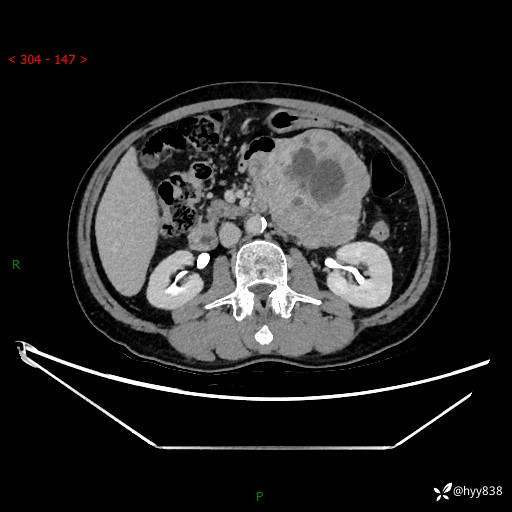

年龄:61岁

主诉:发现腹膜后肿瘤3天

腹部CT平扫+增强(动脉期+静脉期)